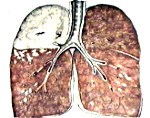

Картина, выявляемая по данным рентгенографии легких, различается в зависимости от формы бактериальной деструкции легких. В типичных случаях легочные деструкции определяются в виде полостей с горизонтальным уровнем жидкости, вокруг которых распространяется воспалительная инфильтрация легочной ткани. При плевральных осложнениях выявляется смещение тени средостения в здоровую сторону, уровень жидкости в плевральной полости, частичный или полный коллапс легкого. В этом случае целесообразно дополнение рентгенологической картины данными УЗИ плевральной полости, плевральной пункции и исследования экссудата.